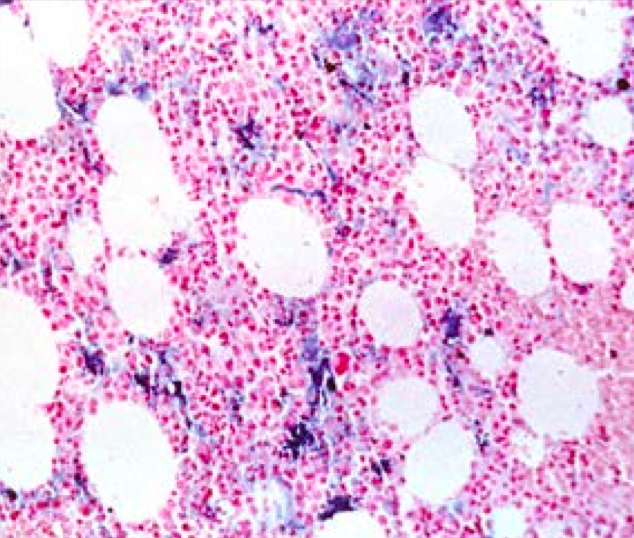

A normal biopsy will appear like the image below when stained with Prussian blue, showing that Fe is present in the marrow.